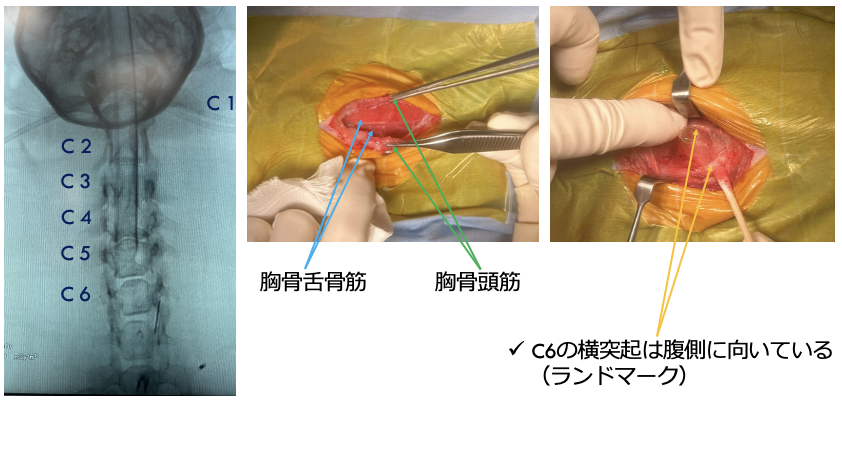

犬の頸部椎間板ヘルニアとは、頚椎と頚椎の間の椎間板が飛び出して、脊髄や神経を圧迫してしまう病気です。症状は、軽度な場合は首を動かすのを嫌がる、抱き上げるとキャンと鳴く、元気食欲低下などが認められます。中等度から重度になると、頸部の痛みが強くなり、ふらつき、四肢麻痺となり起立・歩行不能となります。診断には、CT・MRIが必要となります。軽度から中等度の場合は、内科的に治療することもありますが、重度の場合は、外科的介入が必要となります。外科的な方法としては、腹側スロット術(ベントラルスロット術)が一般的に行われます。椎間板ヘルニアが多発する場合は、背側椎弓切除術を行います。